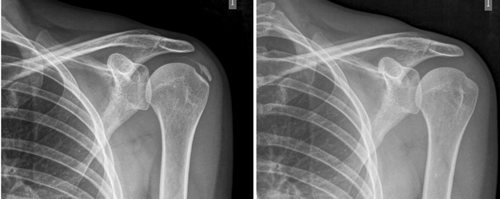

El número promedio de sesiones en nuestra serie fue de 20. El criterio para continuar o suspender el tratamiento fue la evolución radiológica y clínica (Figuras 4 y 5). Las intervenciones se realizaron hasta un máximo de 40 sesiones. Perrón trató a sus pacientes por 9 sesiones (3 sesiones semanales por 3 semanas) (14). Leduc trató con 10 sesiones (3 por semana las dos primeras semanas; y luego una semanal por 4 semanas) (15). Rioja-Toro trató a sus pacientes por 40 sesiones (5 veces por semana) y los evaluó a las 20 y a las 40 sesiones (3). Chico-Álvarez trató a sus pacientes entre 15 y 30 sesiones dependiendo de la evolución radiológica (5 veces por semana) (1).

Fig. 4. Paciente mujer de 47 años con tendinitis calcificante de supraespinoso derecho, de tipo formativa, quien tras 30 sesiones de iontoforesis disminuyó el dolor medido por EVA de 6/10 a 3/10 y la calcificación de 38 mm a 8 mm (valoraciones al inicio, a las 10, a las 20 y a las 30 sesiones, respectivamente).